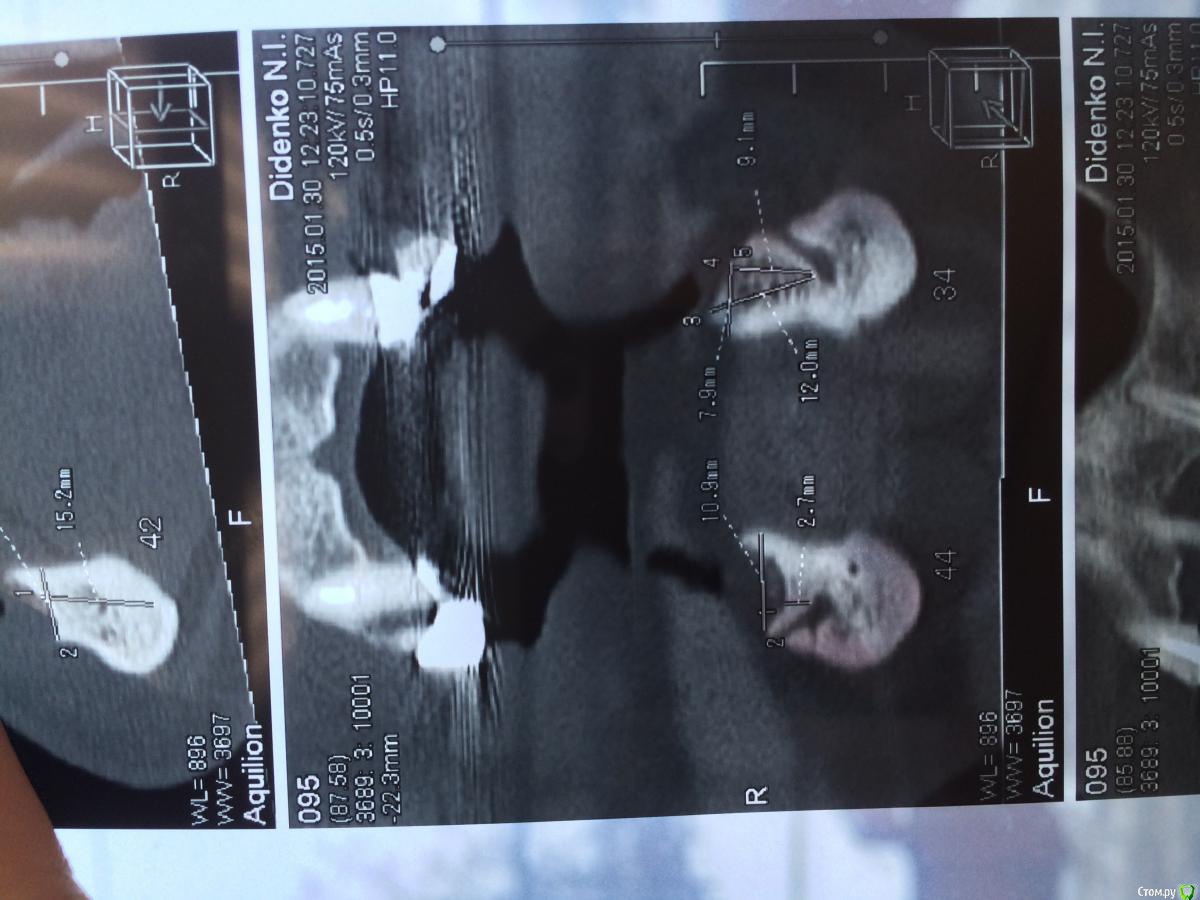

urseva19.05.10 Опубликовано 31 января, 2015 Поделиться Опубликовано 31 января, 2015 Коллеги, в каких позициях на ваш взгляд целесообразнее поставить имплантаты желательно без НКР ( пациент ограничен во времени) что бы в последствии протезироваться съемным протезом на локаторах? На верх не смотрите там все ясно Спасибо! Ссылка на комментарий

Alejandro Опубликовано 31 января, 2015 Поделиться Опубликовано 31 января, 2015 В области 36,46 толщина альвеоляра какая? Ссылка на комментарий

urseva19.05.10 Опубликовано 31 января, 2015 Автор Поделиться Опубликовано 31 января, 2015 10,5 и 9,2 соответственно Ссылка на комментарий

syrovovec Опубликовано 31 января, 2015 Поделиться Опубликовано 31 января, 2015 Ставьте в межментальное 2 или 4, как вам больше нравитсяPs фотки очень неудобно смотреть, срезы замеры не информативные 1 Ссылка на комментарий

Alejandro Опубликовано 31 января, 2015 Поделиться Опубликовано 31 января, 2015 Я бы поставил два межментально в области клыков, и два в области шестёрок тогда. Можно не сильно параллелить - на локаторах это прощается. Ссылка на комментарий

kriokov Опубликовано 31 января, 2015 Поделиться Опубликовано 31 января, 2015 1. выравнивайте гребень2. Позиции 34 , 32, 42, 44, если болты позволяют их субкрестально поставить , то притопите, и ушиться бы двурядно, Ссылка на комментарий

urseva19.05.10 Опубликовано 1 февраля, 2015 Автор Поделиться Опубликовано 1 февраля, 2015 1. выравнивайте гребень2. Позиции 34 , 32, 42, 44, если болты позволяют их субкрестально поставить , то притопите, и ушиться бы двурядно, 1. Всё-таки считаете без НКР не обойтись?2. С 32,42 понятно, а если в области 36,46 установить не будет ли лучше фиксация протеза, да и условия вроде позволяют. Как думаете? Ссылка на комментарий